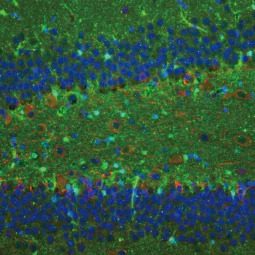

GeneTex is proud to introduce the new recombinant rabbit monoclonal S100 beta antibody [HL2228] (GTX638273) to detect S100 beta in different applications and species.